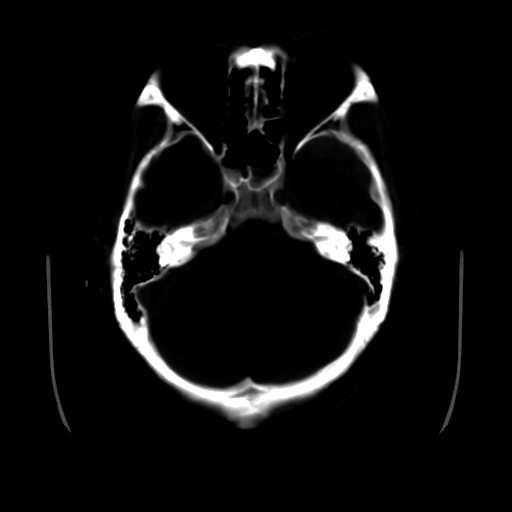

男,51岁,头外伤一小时,呕吐两次。

1)左侧中颅窝蝶骨翼后方硬膜外血肿。2)左侧颞顶部硬膜下血肿。3)蛛网膜下腔出血。4)左侧筛窦及双侧蝶窦炎症(或积血)。5)左侧额部头皮软组织肿胀。

左颞部硬膜外血肿,蛛网膜下腔出血,副鼻窦积液.头皮损伤.